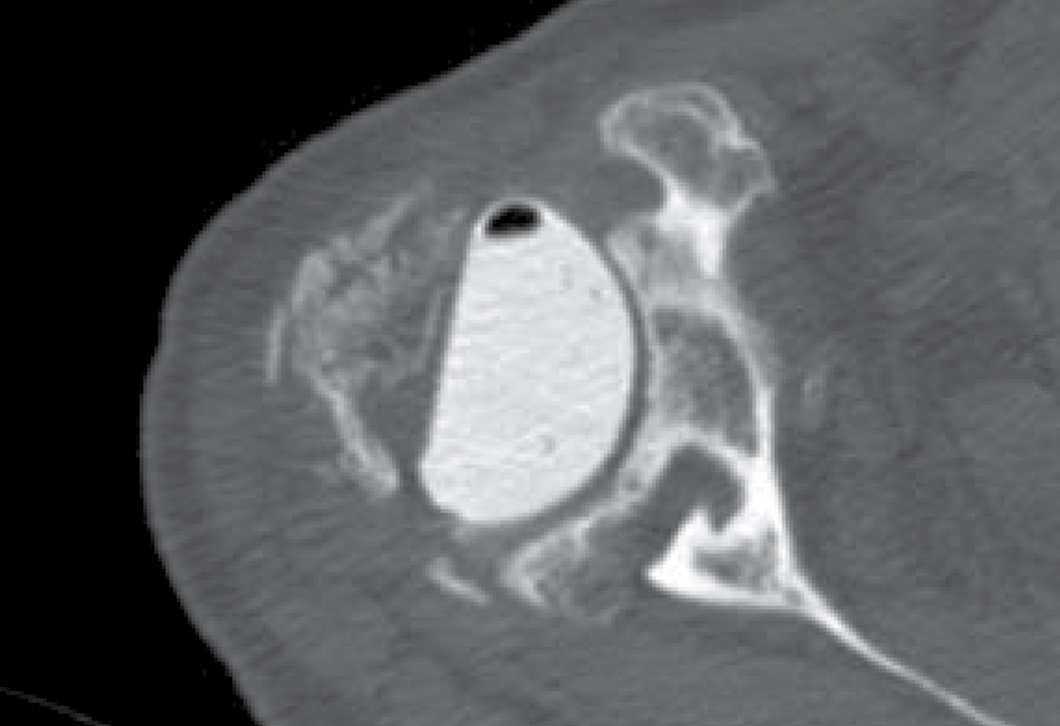

Computed tomography with 3D reconstruction was used preoperatively and showed bony deficiency with a compromised glenoid vault (Fig. 2). The Comprehensive® Vault Reconstruction System (VRS) (Zimmer Biomet, Warsaw, IN) was planned with computer-aided design (CAD) software to create a custom titanium implant. The software allowed for planning of exact screw trajectories to obtain the best purchase in the remaining scapular bone.

Figure 2: CT with 3D reconstruction shows deficient glenoid vault.